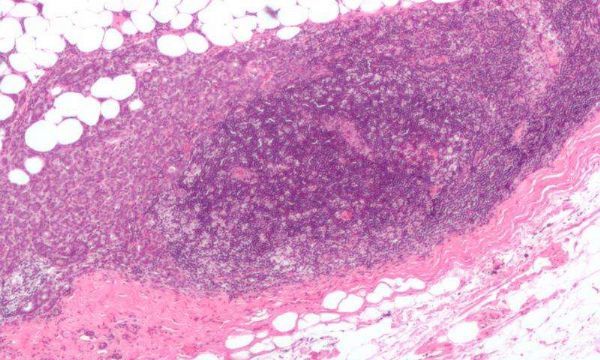

图片来源:Nephron/Wikipedia